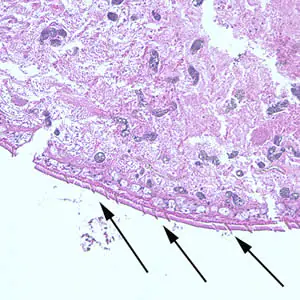

A patient complaining of intermittent symptoms including coughing up blood, fever, and other vague “flu-like” symptoms saw a physician. The patient reported working at a sushi restaurant and eating a raw crab on a dare (Figure A shows a crab similar to the one that the patient ate). Blood tests were ordered and results included peripheral eosinophilia of 10% and a history of bilateral pneumothorax (free air or gas in the pleural cavity). A biopsy yielded a cyst containing a structure 5 mm in length and 2 mm in width. Figure B (40×) and Figure C (100×) show a hematoxylin and eosin (H & E) stained section of the specimen. Figure D (400×) shows an object which measured 80-90 µm by 40-45 µm. Similar objects were found in low numbers in sections of lung tissue. What is your diagnosis? Based on what criteria?

Figure C